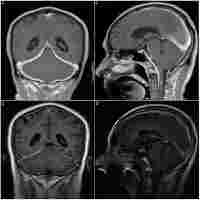

Treatment-responsive case of focal clivus IgG4-related hypertrophic pachymeningitis mimicking meningioma; case report.